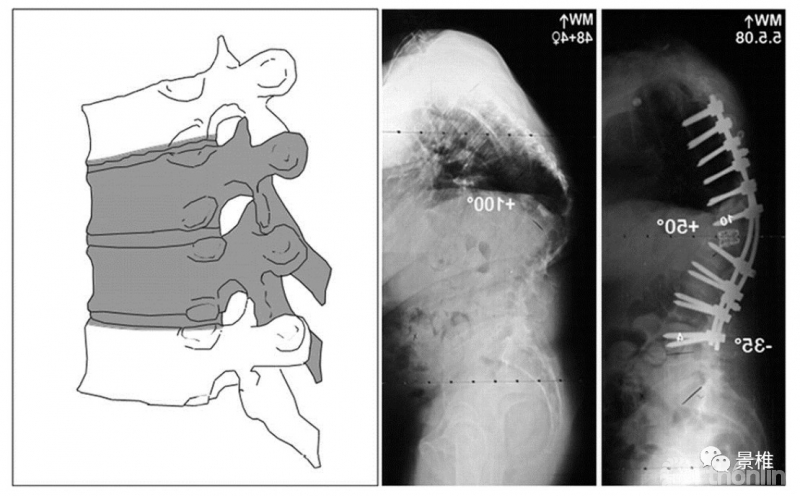

5级 VCR

5级,彻底拿掉一个椎体及上下间盘,在胸椎还包括同序列肋骨。一个椎体的叁柱全部切除了,所以也叫VCR(Vertebral Column Resection)。后凸矫形可达50º。

VCR简明图解:

VCR(vertebral column resection),椎体叁柱切除术。第一步,切除椎体后方结构。

整体椎体结构都被拿掉了,体内原位折棒调整角度,凸侧加压、凹侧撑开复位脊柱序列。

椎间隙植入钛笼,硬膜囊上覆盖明胶海绵之类的保护下,把截除肋骨噼成条,做后方植骨。安装横联。

各级截骨矫形度数简记:级数×10º